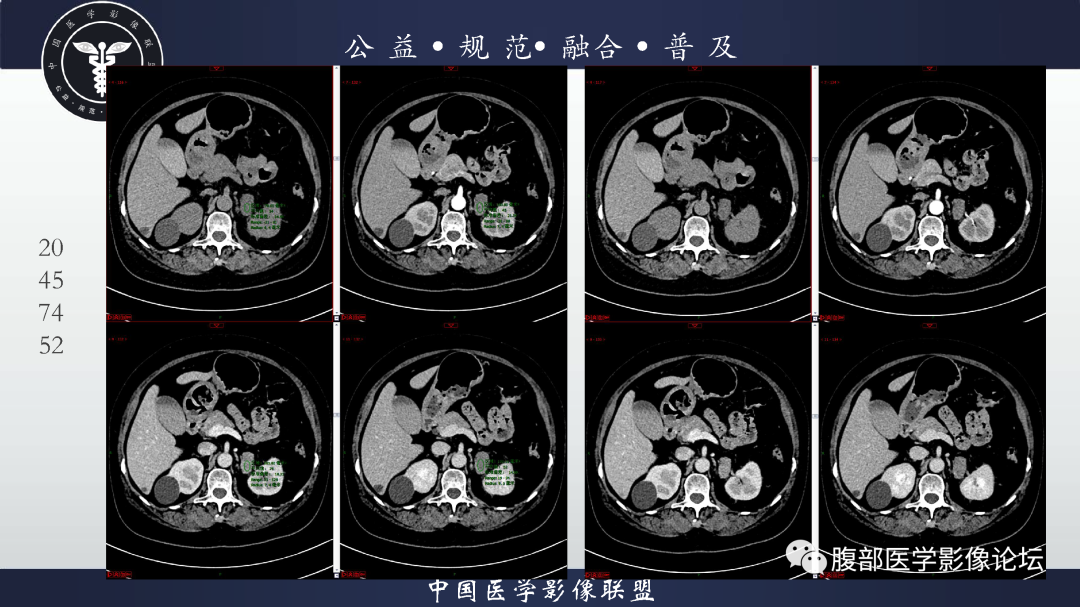

【病例】肾脏透明细胞癌1例CT影像-1